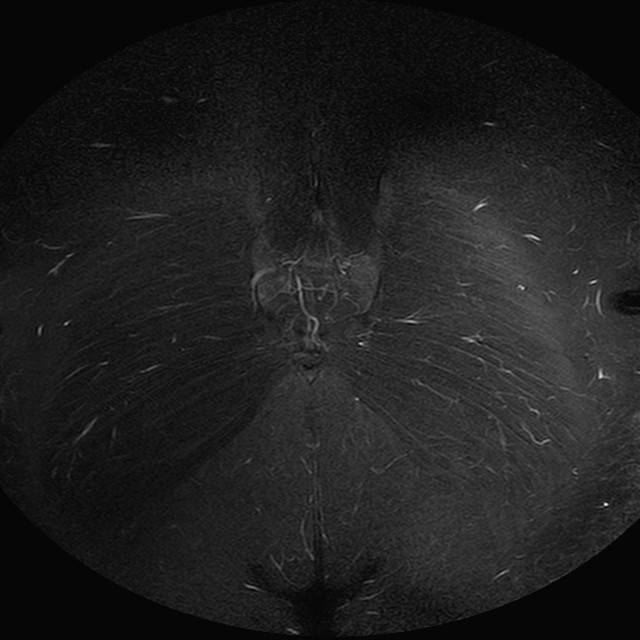

eSTIR

Evidenti e simmetriche alterazioni osteofitosiche in regione coxo femorale con riduzione delle rime articolari. Degenerazione completa del cercine glenoideo. Non attuali segni di versamento articolare. Non segni di edema osseo che escludono attuale algodistrofia od osteonecrosi. Lieve e simmetrica riduzione del trofismo della muscolatura glutea.